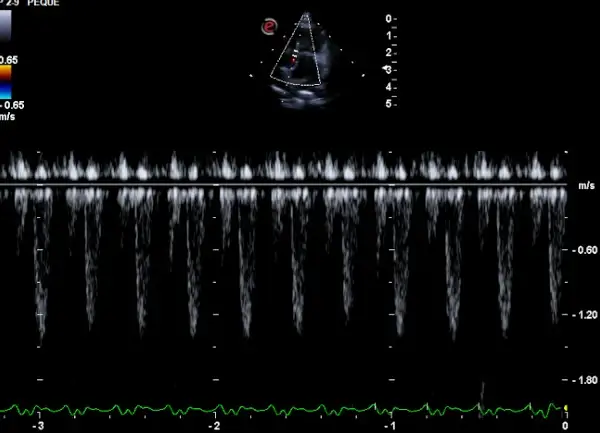

Especialidad Cardiología Felina

CMH Miocardiopatia hipertrofica

Esta condición se caracteriza por el engrosamiento de las paredes del ventrículo izquierdo, lo que puede llevar a una reducción en la capacidad del corazón para bombear sangre de manera eficiente.

En gatos de edad avanzada, la prevalencia de la CMHF aumenta significativamente.

Es fundamental reconocer que la CMHF puede ser asintomática en sus etapas iniciales, lo que subraya la importancia de realizar chequeos cardíacos regulares en gatos adultos y senior.

La ecocardiografía es la herramienta diagnóstica de elección, permitiendo una evaluación detallada de la estructura y función cardíaca.

La cardiología felina está experimentando grandes avances en la última década, mejorando en diagnóstico y tratamiento de los pacientes.

La ecocardiografía es el gold standard para el diagnóstico de cardiomiopatía hipertrófica, la enfermedad cardíaca más frecuente en gatos. Permite medir el grosor de las paredes ventriculares, evaluar la función sistólica y diastólica y detectar trombos intracardíacos que pueden causar embolismo arterial.